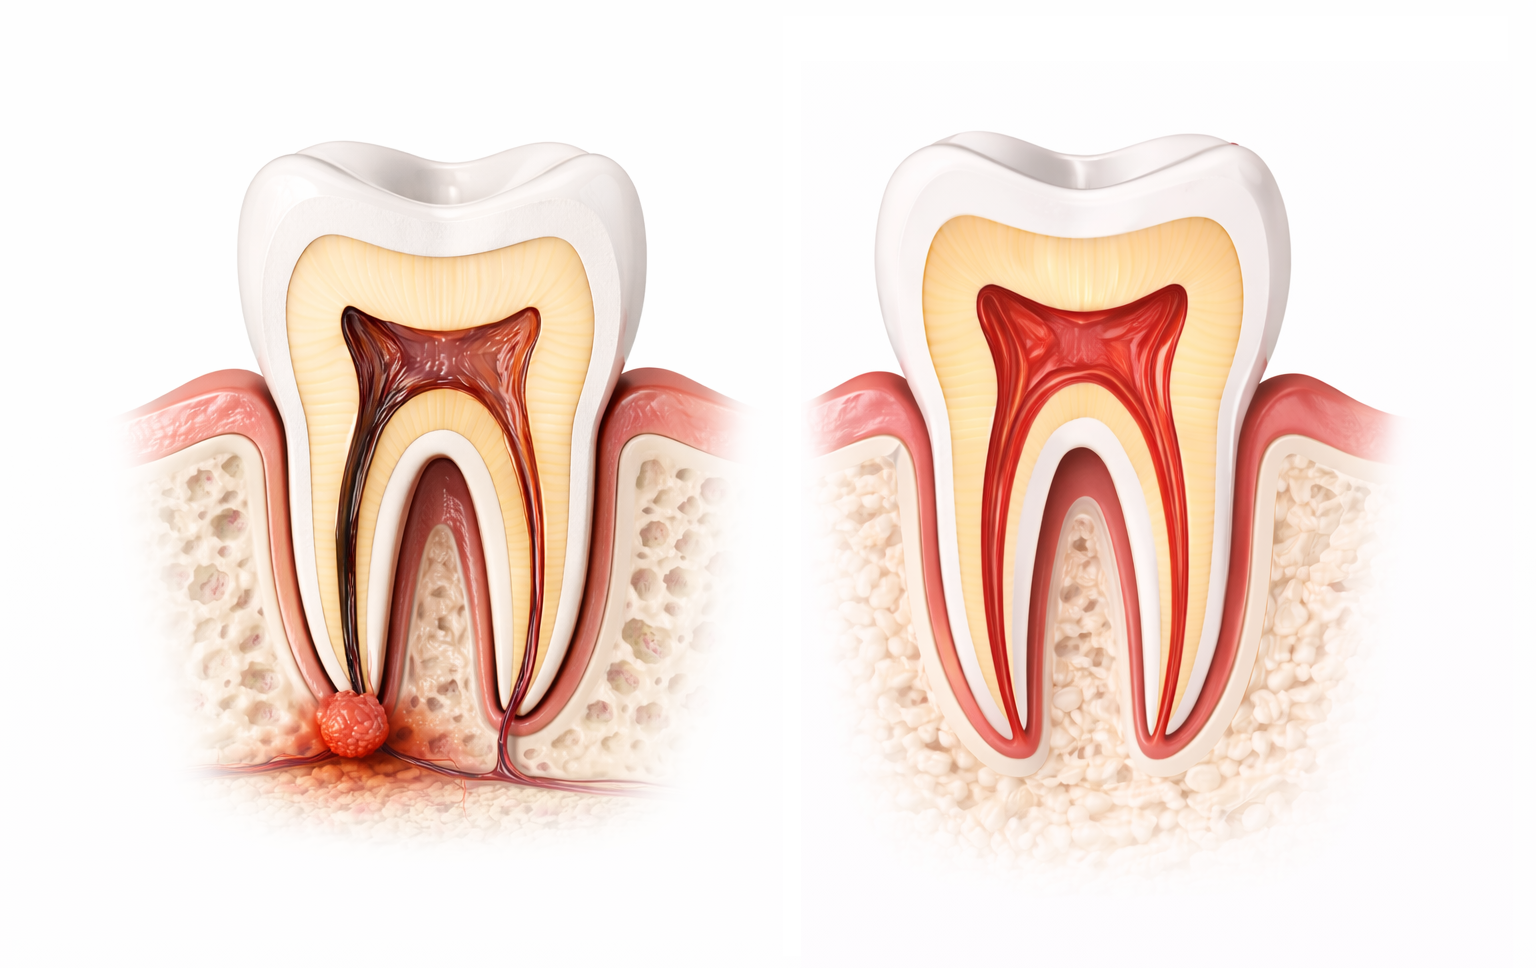

Eine Wurzelbehandlung ist eine zahnmedizinische Behandlung, bei der entzündetes oder abgestorbenes Gewebe im Inneren eines Zahns entfernt wird. Dieses Gewebe befindet sich im sogenannten Wurzelkanal und enthält Nerven sowie Blutgefäße. Dringen Bakterien – zum Beispiel durch tiefe Karies – bis in diesen Bereich vor, kann es zu einer schmerzhaften Entzündung kommen. Der medizinische Begriff dafür ist Wurzelkanalbehandlung.

Ziel der Wurzelbehandlung ist es, den natürlichen Zahn zu erhalten und die Entzündung dauerhaft zu beseitigen. Dafür werden die betroffenen Wurzelkanäle sorgfältig gereinigt, desinfiziert und anschließend bakteriendicht verschlossen. So kann der Zahn trotz vorheriger Schädigung weiterhin im Mund verbleiben und seine Funktion erfüllen.

Eine Wurzelbehandlung wird immer dann notwendig, wenn sich das Innere eines Zahns entzündet hat: Das sogenannte Zahnmark. Das passiert meist nicht plötzlich, sondern ist das Ergebnis eines längeren Prozesses – zum Beispiel, wenn Karies immer weiter in die Tiefe vordringt und schließlich den Zahnnerv erreicht.

Unbehandelt verschwindet so eine Entzündung nicht von allein. Im Gegenteil: Sie kann sich weiter ausbreiten und langfristig dazu führen, dass der Zahn nicht mehr zu retten ist. Genau hier setzt die Wurzelbehandlung an – sie entfernt die Ursache der Entzündung und gibt dem Zahn die Chance, erhalten zu bleiben.

Im weiteren Verlauf kann sich unterhalb der Zahnwurzel ein sogenannter Abszess bilden – eine Ansammlung von Eiter, die mit Schwellungen, Druckgefühl und starken Beschwerden einhergehen kann. In solchen Fällen wird die Behandlung meist aufwendiger.

Nach dem Öffnen des Zahns wird das entzündete oder abgestorbene Gewebe aus den feinen Wurzelkanälen entfernt. Mit speziellen Instrumenten werden die Kanäle Schritt für Schritt gereinigt. Ziel ist es, alle Bakterien und Rückstände vollständig zu beseitigen.

Sind die Kanäle gereinigt, werden sie gründlich desinfiziert, um verbliebene Keime zu entfernen. Anschließend werden die Kanäle mit einem gut verträglichen Material dicht verschlossen. So wird verhindert, dass erneut Bakterien in den Zahn eindringen.